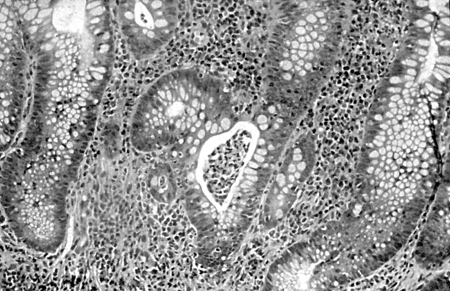

Colite ulcerativa

Amostras de biópsia do cólon exibindo inflamação severa da mucosa, formação de abscessos crípticos, atrofia glandular leve e distorção, sugerindo uma fase ativa da colite ulcerativa; coloração de hematoxilina e eosina, aumento de 400x.

Extraído de: Iannone F, Scioscia C, Musio A, et al Leucocytoclastic vasculitis as onset symptom of ulcerative colitis Ann Rheum Dis 2003 Aug;62(8):785-6; usado com permissão